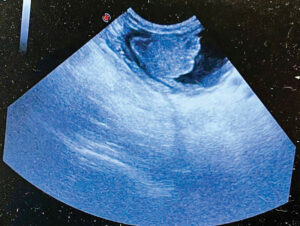

aFAST identifies a bladder mass in a 15-year-old schnauzer. Photos courtesy Dr. Erica Tramuta-Drobnis

1) Figure 1. A 15-year-old M/N schnauzer with a four-month history of urinary accidents and dribbling urine presented with hematuria and an inability to urinate. This image clearly shows a large bladder mass, accounting for clinical signs.